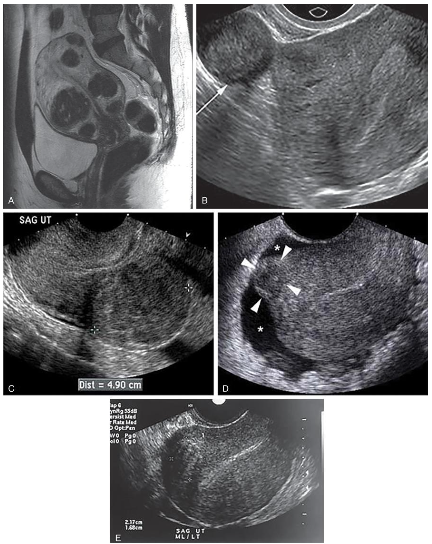

Also called Myomas, Fibroids, and Fibromyomas

Most common pelvic tumor

More common in African American women nulliparous (never borne offspring)

Smooth muscle cell composition

Liquefaction, necrosis, hemorrhage, and ultimate calcification may take place.

Degeneration occurs when myomas outgrow their blood supply; calcification

May be pedunculated

Sonographic Findings of Leiomyomas

• Uterine enlargement or irregular uterine wall contour with a heterogeneous myometrial texture pattern.

• Look for contour distortion along the interface between the uterus and bladder.

• The myomas alters the normal homogeneous myometrium

• Myomas can be associated with endometrial infection and cancer.

• Blood debris and polyps can artifactually widen the endometrium; therefore definitive diagnosis of the

cause of abnormal bleeding require an endometrial biopsy.

• Cystic degeneration can occur during pregnancy and cause pain. Doppler should be used to assess

the vascularity of myomas.

The sonographic study should include measurement of the uterus in three dimensions: (1) cervix to

fundus, (2) widest anteroposterior diameter, and (3) widest transverse diameter at fundus diameter.

The texture of the myoma (calcific, complex, or anechoic), size, and location are described.

Individual myomas are measured if they are discrete.

The shape of the endometrial complex and its thickness are also described; alterations in the

endometrial border will be evident if a myoma is present. This is especially important in women with a

history of abnormal bleeding.

Myomas can be associated with endometrial infection or cancer. Blood debris and polyps can

artifactually widen the endometrium; therefore, definitive diagnosis of the cause of abnormal bleeding

might require an endometrial biopsy or sonohysterography.

Although ultrasound is used to identify myomas in women with abnormal bleeding, uterine

enlargement, or infertility, MRI—with its tissue differentiation characteristics—can be more

sensitive for evaluating the exact location, size, and number of myomas.